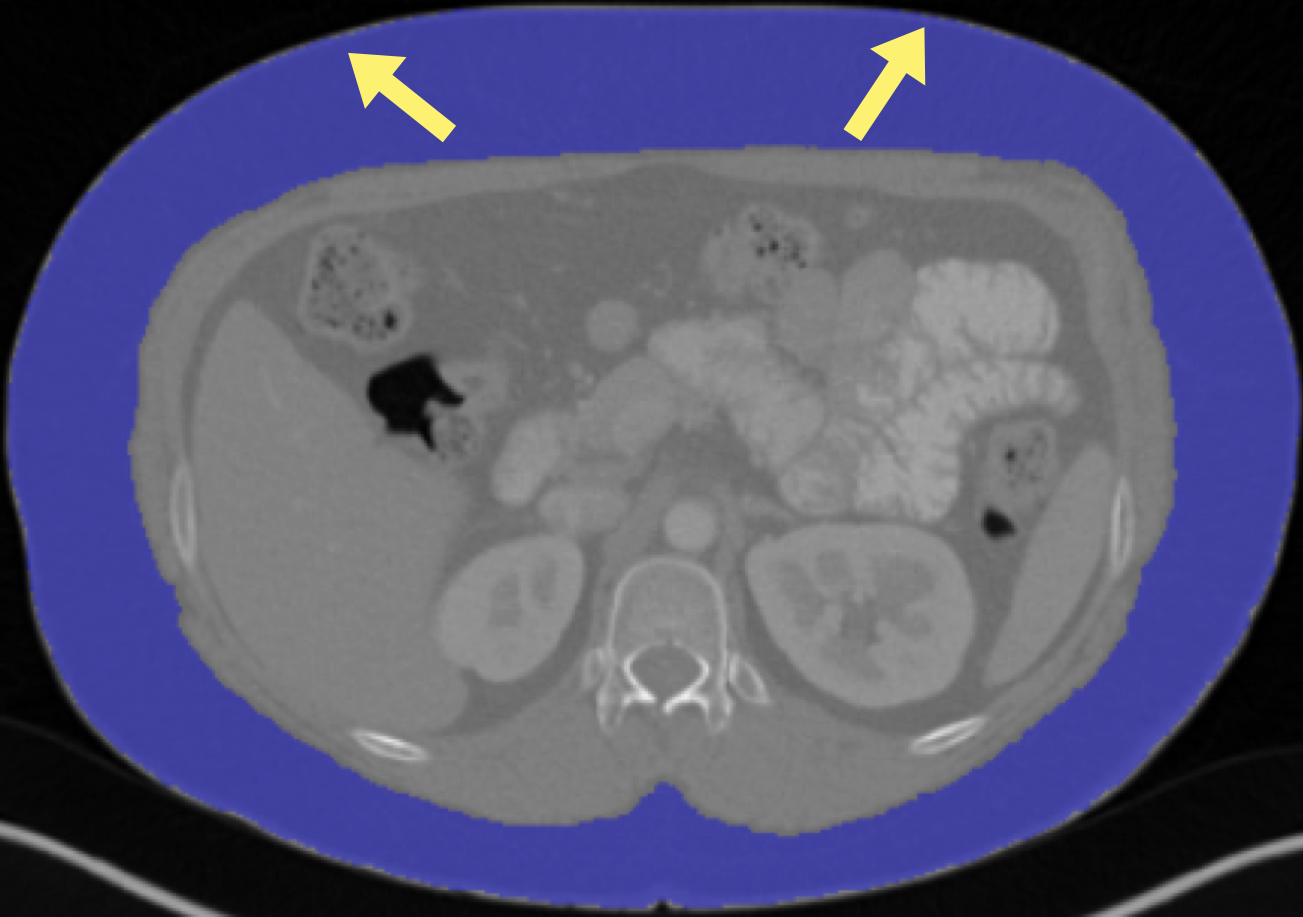

5.2 Qualitative evaluation

Fig. 2 demonstrates the L3 segmentation results and their corresponding body composition metrics (muscle density, VAT/SAT ratio, muscle area/volume, and SMI) for five selected patients. These examples were carefully selected to reflect extreme variations in body composition within the Demographic Analysis dataset, including exceptionally low and high values of muscle density (Patient 3 and Patient 2, respectively), VAT/SAT ratio (Patient 2/5 and Patient 4), muscle area (Patient 1 and Patient 2), and SMI (Patient 1 and Patient 5).

For a more comprehensive qualitative evaluation across patients with varying body composition levels, including all four metrics in both 2D and 3D visualizations, the figures are presented in Appendix E.

Notably, as shown in figure 2 result, there’s no simple correlation between the four body composition metrics. For example, Patient 2 with the highest muscle density does not exhibit the highest skeletal muscle index. More precise relationship analysis based on Pearson Correlation coefficient for each body composition metrics pair is shown in Appendix F.